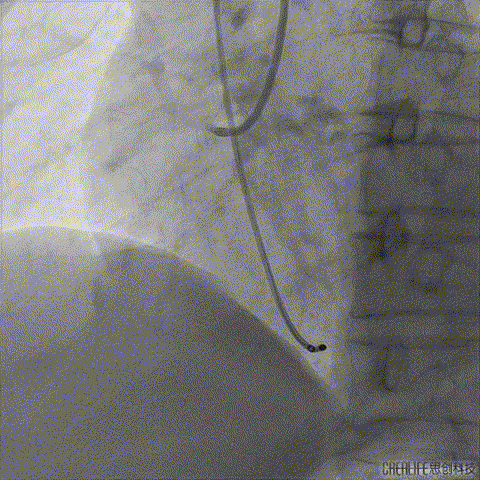

TaurusElite输送系统轻松过弓、跨瓣,AV23瓣膜瓣环上约2mm释放;

TaurusElite轻松过弓

瓣膜释放